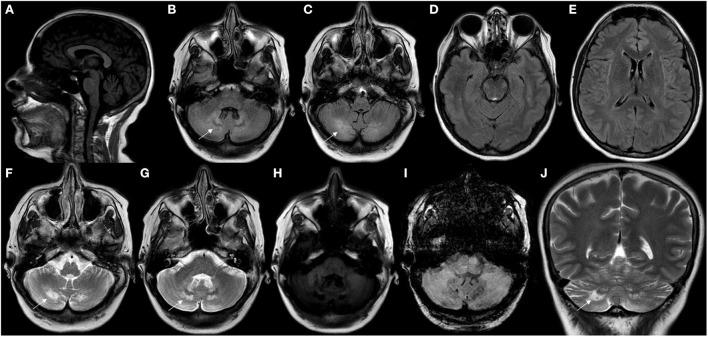

Cerebrotendinous Xanthomatosis represents a rare and underdiagnosed inherited neurometabolic disorder due to homozygous or compound heterozygous variants involving the gene. This bile acid metabolism disorder represents a key potentially treatable neurogenetic condition due to the wide spectrum of neurological presentations in which it most commonly occurs. Cerebellar ataxia, peripheral neuropathy, spastic paraparesis, epilepsy, parkinsonism, cognitive decline, intellectual disability, and neuropsychiatric disturbances represent some of the most common neurological signs observed in this condition. Despite representing key features to increase diagnostic index suspicion, multisystemic involvement does not represent an obligatory feature and can also be under evaluated during diagnostic work-up. Chenodeoxycholic acid represents a well-known successful therapy for this inherited metabolic disease, however its unavailability in several contexts, high costs and common use in patients at late stages of disease course limit more favorable neurological outcomes for most individuals. This review article aims to discuss and highlight the most recent and updated knowledge regarding clinical, pathophysiological, neuroimaging, genetic and therapeutic aspects related to Cerebrotendinous Xanthomatosis.

脑腱黄瘤病是一种罕见且易被漏诊的遗传性神经代谢疾病,由涉及该基因的纯合或复合杂合变异引起。这种胆汁酸代谢紊乱是一种关键的潜在可治疗性神经遗传病,因为它最常出现的神经系统表现范围广泛。小脑共济失调、周围神经病变、痉挛性截瘫、癫痫、帕金森综合征、认知衰退、智力残疾和神经精神障碍是这种疾病中一些最常见的神经学体征。尽管这些是提高诊断指数怀疑度的关键特征,但多系统受累并非必然特征,在诊断检查过程中也可能未得到充分评估。鹅去氧胆酸是治疗这种遗传性代谢疾病的一种著名且成功的疗法,然而,它在多种情况下无法获取、成本高昂且常用于病程晚期的患者,这限制了大多数患者获得更理想的神经学转归。这篇综述文章旨在讨论和强调关于脑腱黄瘤病的临床、病理生理、神经影像学、遗传学和治疗方面的最新知识。